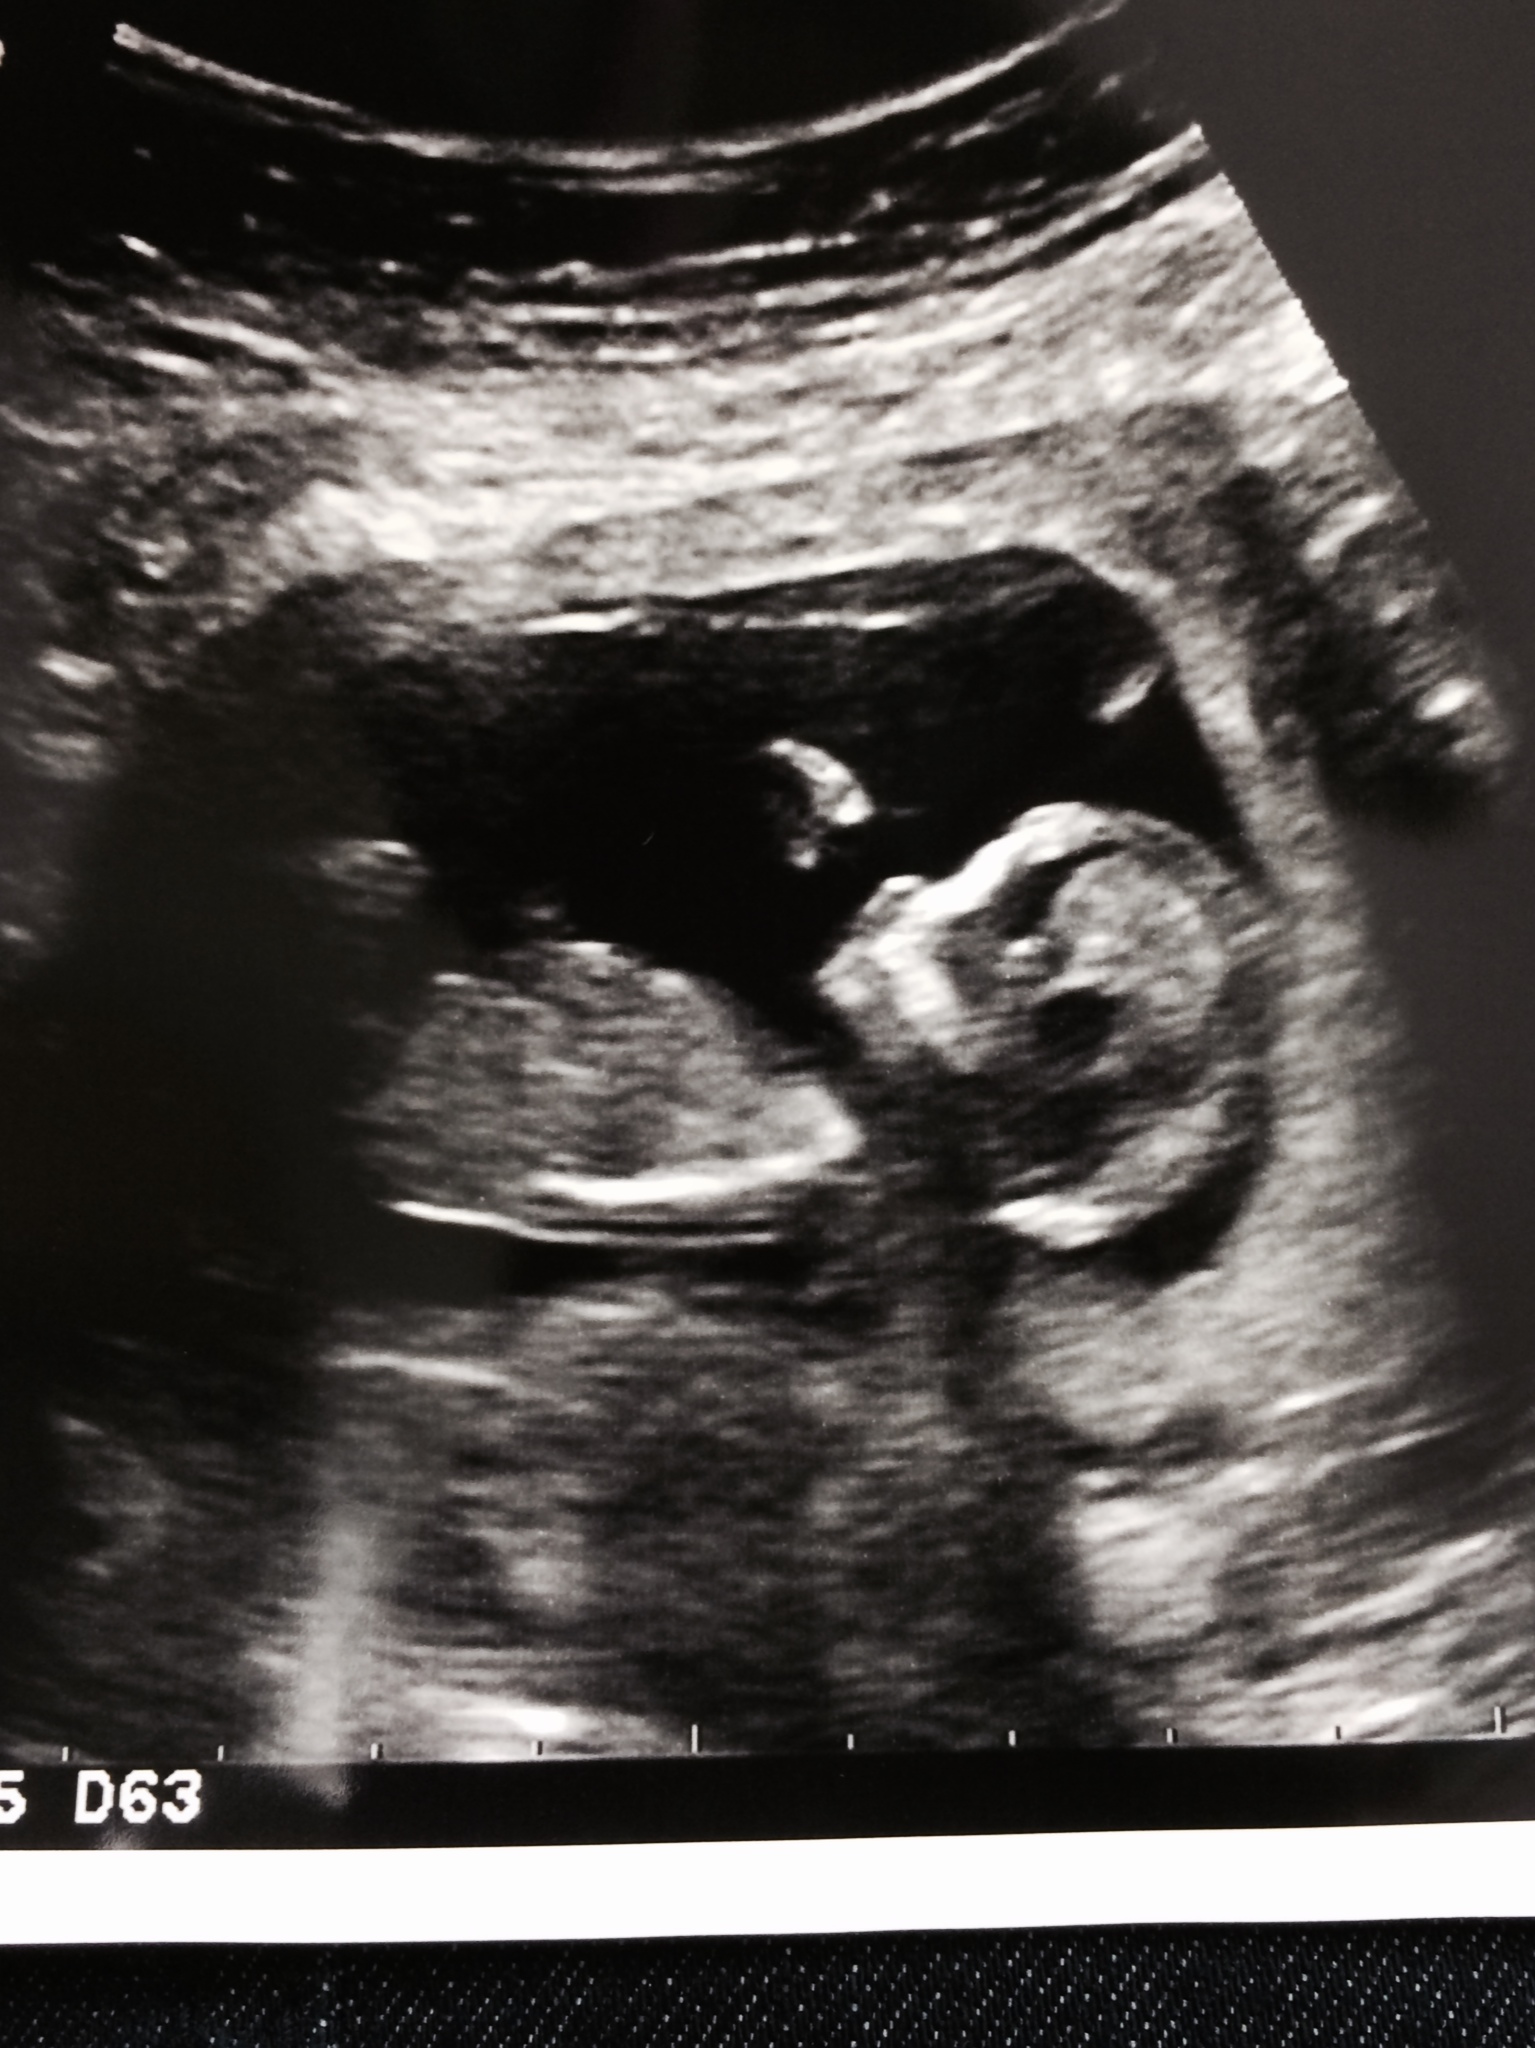

Followup I had our appt yesterday! Thank god everything went well! YAY! Baby was just bouncing & rolling around everywhere!! She had a tough time measuring the NT because of the bouncing! (hehe) HB was at 161!! YAY! We almost got to count the fingers, because baby was waving at us!! So exciting!! Now hoping all the first tri screening comes back with good news!! OB said we'd hear in about a week! Next appt 4 wks!! Now....onto growing a happy & healthy baby!

Had my 12 week appointment today. NT scan looked perfect and baby was so big!

Had my first appointment today! (11w3d) was super nervous and expecting the worst. Very excited and relieved that everything was perfect. AND I loved my dr! I'm a FTM and was nervous that we weren't going to be a good match. #:-S so glad that's over!

Had a quick check in appointment today at 13 weeks exactly. Dr. found the heart beat and I'm measuring right on track. Monday is my NT scan can't wait for another us.